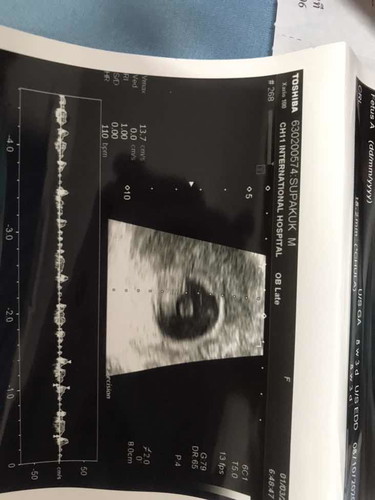

ตอนนี้ได้ 10W แล้วคะ ตอนเช้าชอบมีหยดเลือดสีน้ำตาลๆออกมาประมาน 1-2 หยด พอติด กกน. จะมีออกมาประมาน 2-3 วัน จากนั้นก้หยุดไป ผ่านไปประมาน 3 วัน มีออกมาอีก ตอนเช้าเหมือนเดิม ไปหาหมอมาแล้ว หมอให้ยากันแท้งมากิน แต่ไม่สบายใจเลยคะ กลัวลูกจะไม่อยู่กับเรา เคยแท้งน้องมาแล้ว 2 ครั้ง ประมาน 5-6W แม่ๆคนไหน เคยมีอาการแบบนี้บ้างไหมคะ #รบกวนขอคำแนะนำหน่อยคะ #ขอบคุณคะ